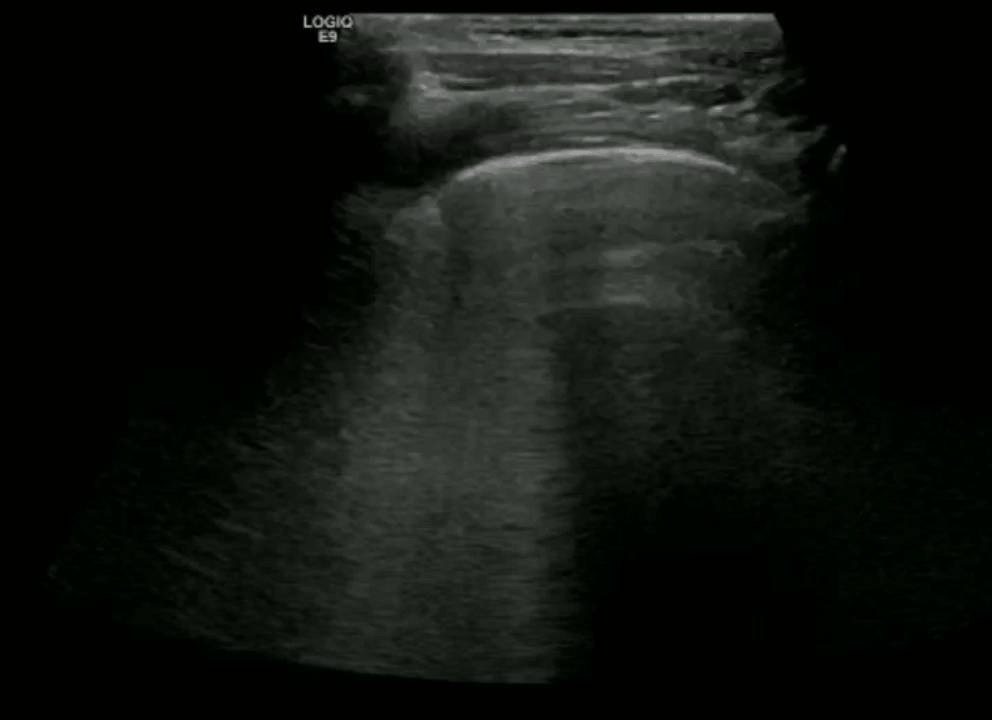

Large volume pleural effusion

Large volume echogenic pleural effusion

Pleural effusion is a build up of fluid between the layers of the pleura. Scanning subcostally will show fluid above the diaphragm. Scanning intercostally will show fluid anterior the lung. Common causes for pleural effusion is infection, inflammation and malignancy.

The fluid can be anechoic or echogenic in cases of increased exudates, empyema, hemothorax and chylothorax (lymph collection). There may also be septations.